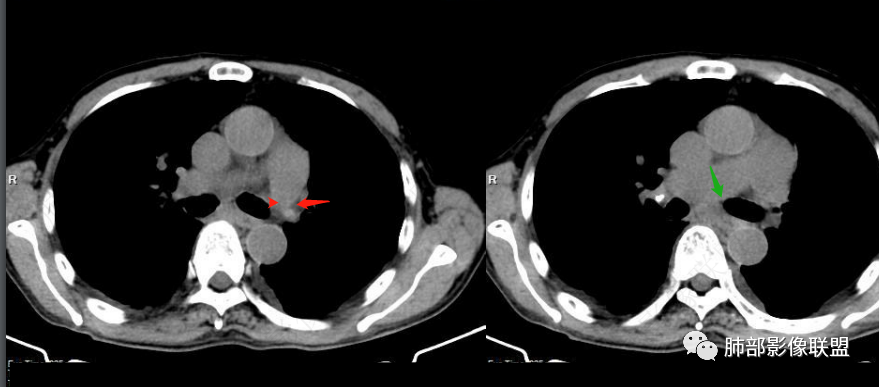

看一下影像,肺动脉粗大,大于升主动脉

从肺动脉的主体分析:左肺动脉好像起始部就开始狭窄。

现在给的图像:是鼠尾状狭窄,而不会局部膨隆,远端细小那种。

右侧的肺动脉增粗肯定与代偿有关。

现在的问题是自左肺动脉狭窄的原因:是急性栓塞?炎性病变?慢性血栓?

4、肺动脉改变:左肺动脉起始部突然狭窄(右肺动脉代偿增大——继发肺内改变)

7.肺动脉主干扩张,左侧肺动脉主干见混杂密度影,上下肺动脉似不能连续追踪。

(增强:左肺动脉充盈缺损、闭塞)